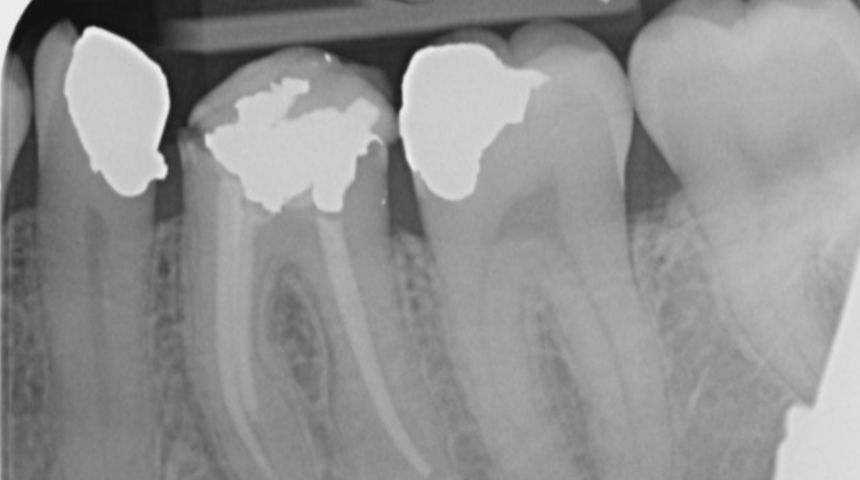

Take a look at some of our recent cases below!